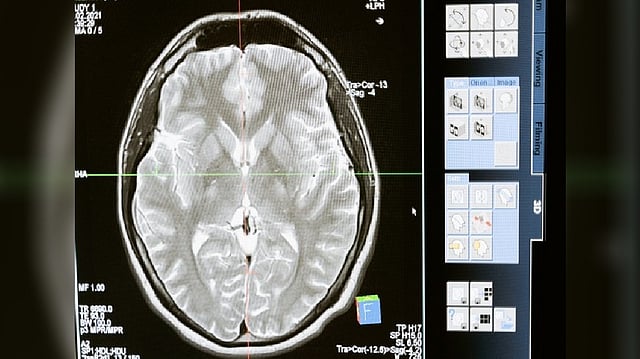

Representative Image

Parkinson's is a disorder that features the deaths of neurons in a characteristic pattern of spread through the brain, normally unfolding over decades.